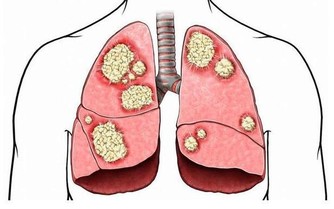

對於人體來說,這部分營養無法被消化,也無法被利用,但這並不意味著它們沒用。這時身體內的不法分子,如潛在的腫瘤因子等就會接收這些“廢物”,供自己享用,一旦時機成熟就會變成令人談之色變的腫瘤。

為什麼人會生病,三高、腫瘤越來越多? 都源於這“兩個字”!